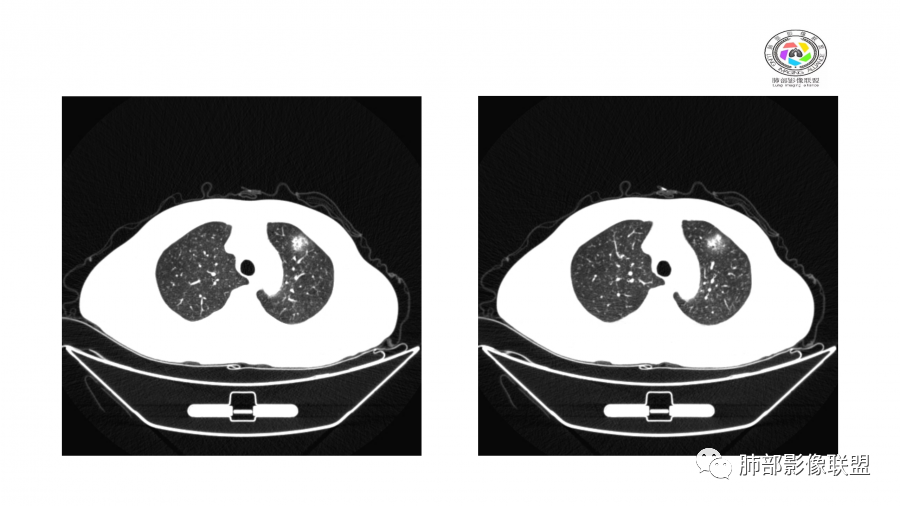

中年男性,高血压,肾功能衰竭,贫血病史,尿潜血阳性。3.8双肺野多发斑片磨玻璃实变影,结节影,边缘模糊,周围有晕征,内见支气管充气征,主要沿支气管血管束分布,部分胸膜下分布,3.12号病灶有吸收好转,4.8号斑片实变影基本吸收,主要沿支气管血管束分布结节影,边缘平直收缩,4.28病灶大部分吸收好转,双肺支气管血管束增粗,有少量结节影。考虑ANCA相关性血管炎可能性大,第一次片子觉得隐球菌不排除,但是后面没有抗真菌治疗就吸收了,觉得隐球菌可能性不大。

一月后:

病灶此起彼伏

患者,男,49岁,初次以头晕呕吐肾功能异常入院,后期伴双下肢水肿,CT示双肺多发斑片及结节影,部分周围伴晕,部分内部可见支气管穿行,多次复查可见部分病灶略吸收及新发病灶出现,最后一次复查双肺多发磨玻璃样改变,综合考虑血管炎,最后一次伴肺水肿可能

影像:双肺散在实变影及毛玻璃影,实性病变周围可见晕征,病灶于肺外围区域优势分布,病变区引流支气管未见增厚,考虑血管相关病变;3月、4月复查CT提示肺内病灶呈游走性,此起彼伏。

胸部CT:双肺多发实性斑片影,散在GGO。实性斑片周围可见晕征、边缘模糊不清,病灶于肺外围区域优势分布。肺门区血管影增粗,支气管套袖,目测肺动脉增粗。3月、4月复查肺内实性斑片病灶呈游走性,此起彼伏。